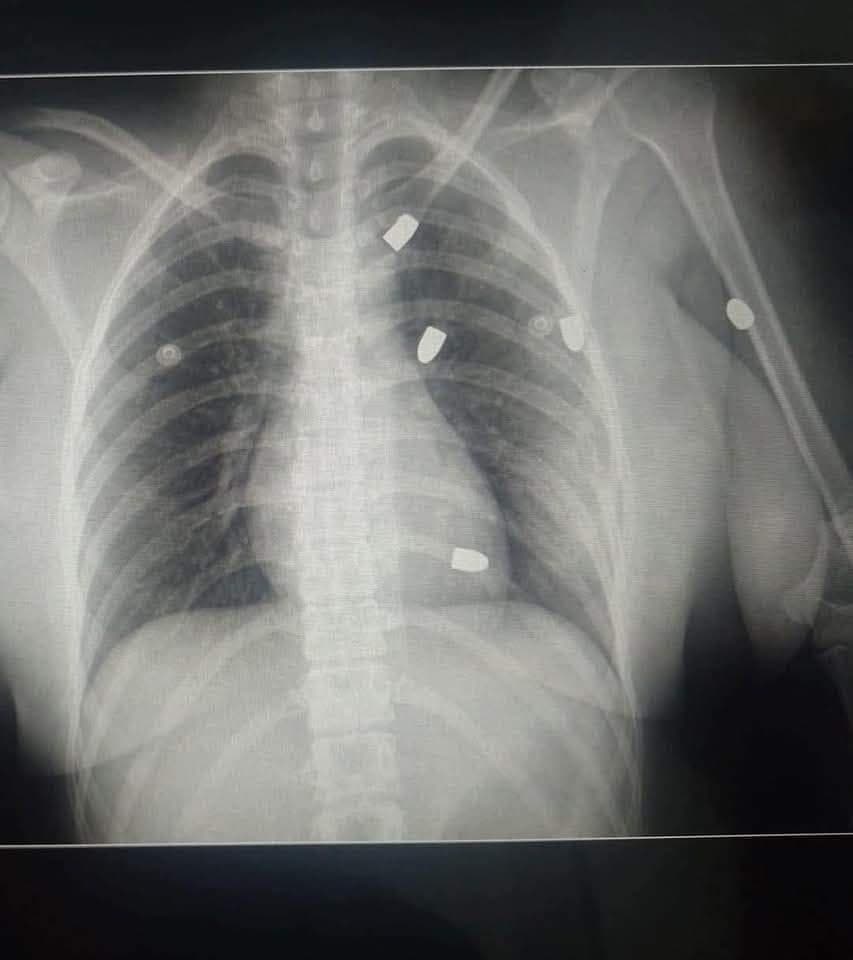

"Gracias a Dios estoy viva"

Diana "N" sigue hospitalizada; reportan su estado de salud como grave